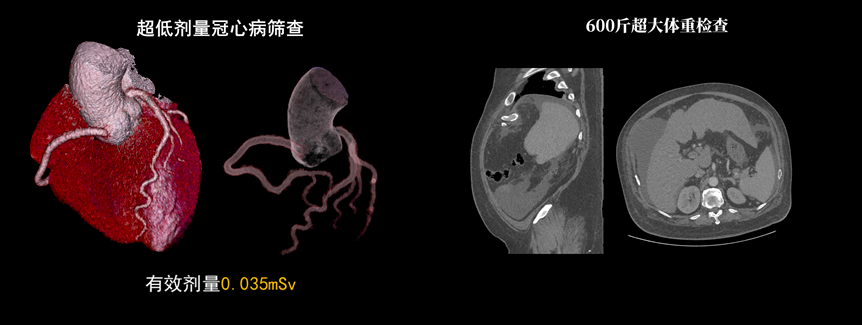

該設(shè)備除具備普通CT的功能外,還具備速度快、精度高、智能化、高效能、微劑量、大孔徑等優(yōu)勢。16厘米Z軸探測器、23毫秒時(shí)間分辨率,聯(lián)影天河640CT讓冠脈CTA檢查擁有“不選擇”的權(quán)利。搭載的一站式聯(lián)合掃描技術(shù),輔以便捷高效的后處理功能,AI精準(zhǔn)血管分割,自動(dòng)預(yù)處理加載,逐支血管觀察,全時(shí)提效,可實(shí)現(xiàn)一次注射造影劑獲取多部位CTA、CTP和4D動(dòng)態(tài)圖像,不僅可以助力腦卒中解決方案,還可助力腦血管畸形、腦動(dòng)脈瘤等其他腦血管病的結(jié)構(gòu)和功能評估。

液態(tài)金屬軸承球管,陽極直冷技術(shù),提供30MHU球管熱容量,可高通量連續(xù)掃描。AI劑量調(diào)制、迭代重建等復(fù)合劑量控制方案,為體檢患者提供優(yōu)化劑量掃查。82cm大孔徑,讓大體型患者檢查更加舒適。

天河640CT的寬體探測器單圈掃描即可覆蓋全心臟,搭配快速機(jī)架轉(zhuǎn)速和獨(dú)家AI冠脈追焦技術(shù),可實(shí)現(xiàn)單心動(dòng)周期內(nèi)無限心率、無限心律的冠脈成像,對于嚴(yán)重心律不齊、房顫、房撲,超高心率等情況,天河640CT都能在單心動(dòng)周期內(nèi)獲得優(yōu)質(zhì)圖像。